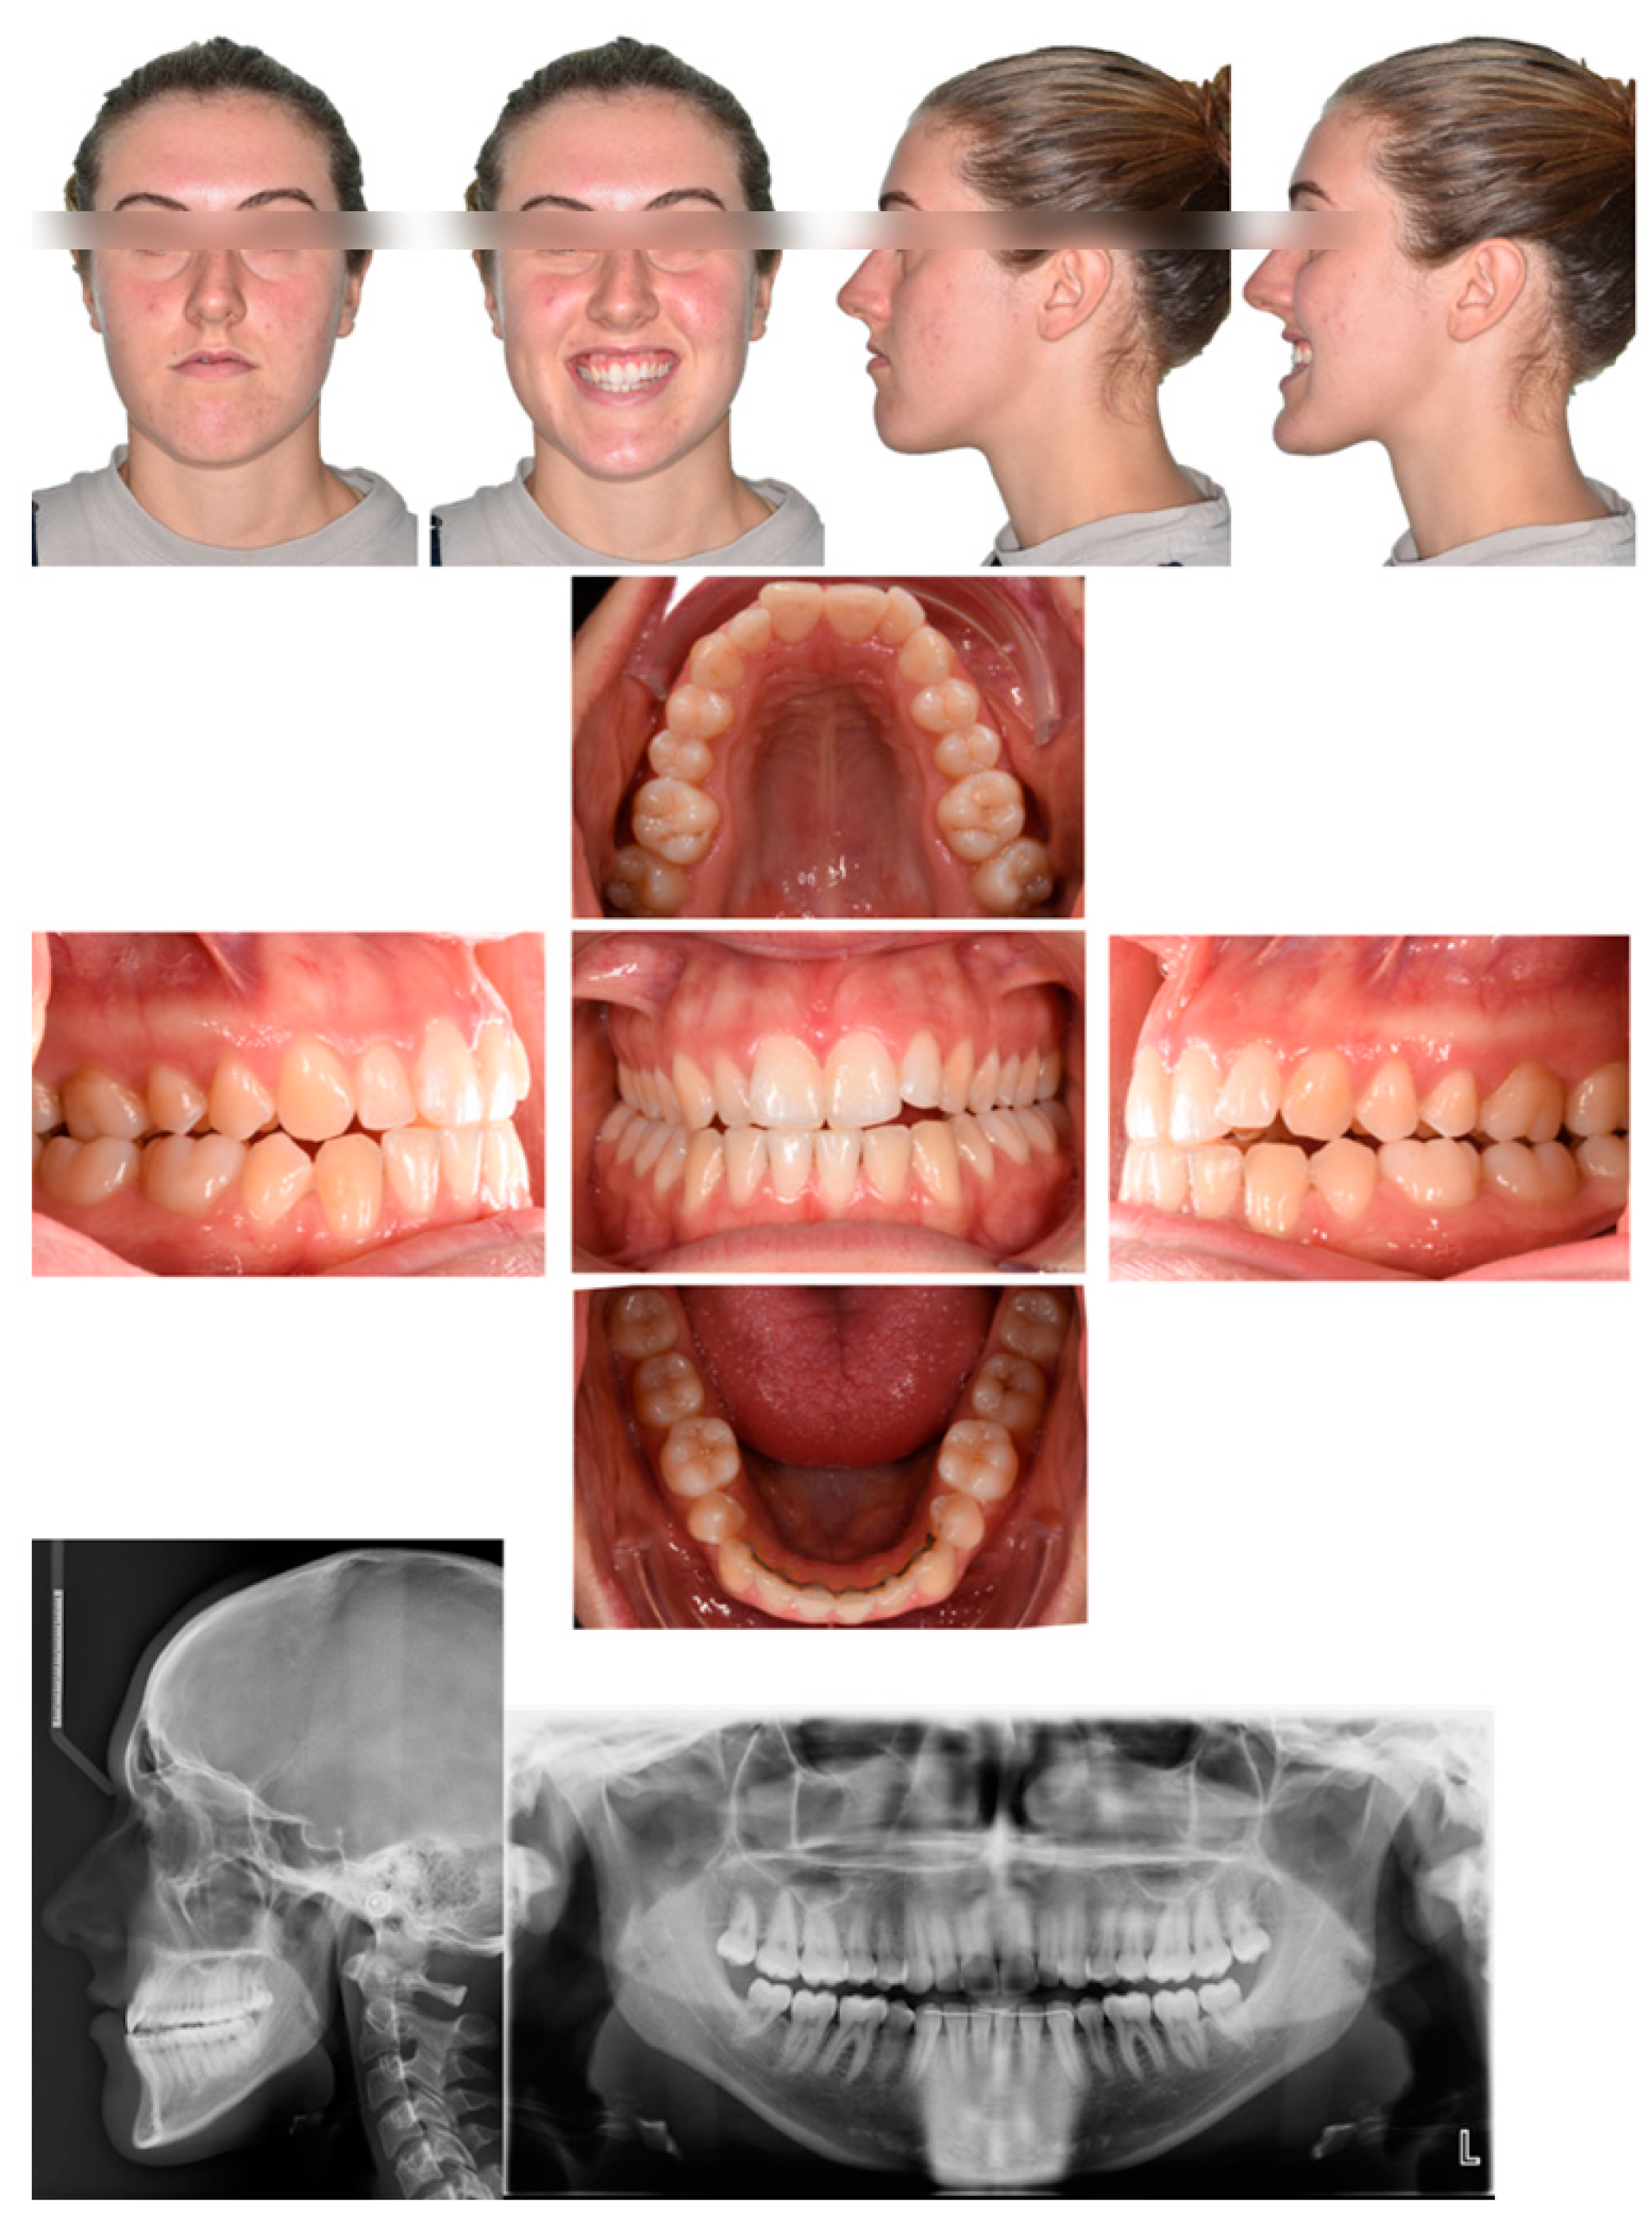

2.1. Diagnosis and Individual Treatment Planning